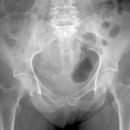

HüftTEP Luxation